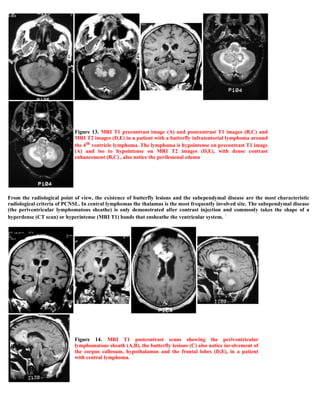

A 32-year-old male presented with a single grand mal seizure. CT scans showed extradural masses in the left parietal and frontal regions, compressing the brain and ventricles. Surgery revealed nodular dural thickening without brain infiltration. Biopsy diagnosed non-Hodgkin B-cell lymphoma. Further staging found extensive extraneural disease, though the CNS manifestations were the initial presentation. The patient was referred for oncology management for epidural secondary CNS lymphoma.